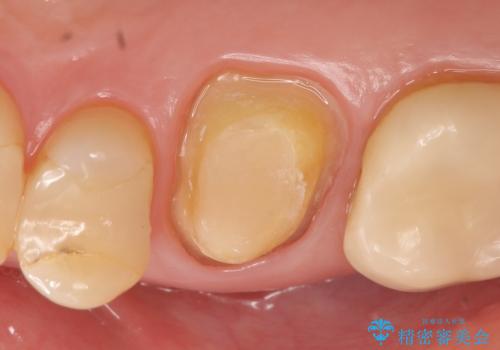

- 他院にて右上6の神経が死んでいるため根管治療が必要だと言われ当院にいらっしゃった方の症例です。

X線上で根尖病変を認めたため根管治療を行い、その後オールセラミッククラウンによる補綴を行いました